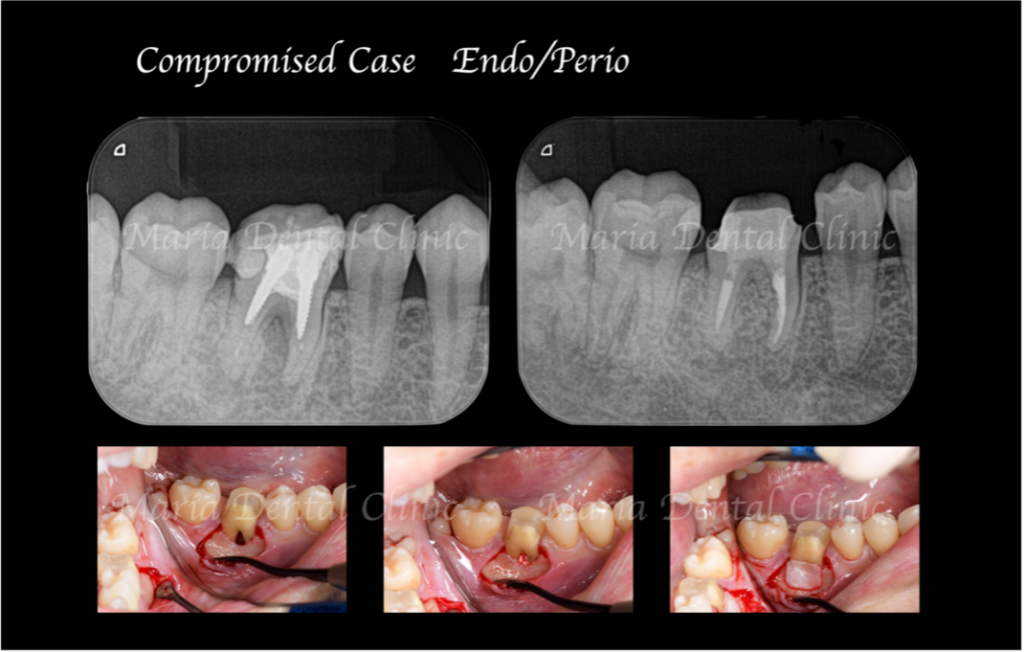

当院での初診時の検査でレントゲンを確認すると、歯冠(歯肉の上に出ている歯の部分)に人工的な透過像が確認でき、前医での治療の際に、偶発的に歯に穴(穿孔・パーフォレーション)が開けられてしまったことが予想できました。また、歯肉(歯ぐき)が大きく腫れあがり、限局的な歯周ポケットが確認される上に、穴のあいている部分と歯周ポケットが交通している可能性も考えられるなど、状況は複雑化していました。

顕微鏡下で根管内を確認すると、レントゲン透過像通りに穴があいていること(穿孔)が確認され、実際の根管は治療が手つかずのままでした。

今回は根管形態が複雑ではなかったため、初回で根管内をすべて洗浄後、根管充填と穿孔修復(パーフォレーションリペア)を行い、2回目の治療にて、歯の土台を作る支台築造処置を終了させました。

根管治療終了1ヶ月後に経過観察を行い、術前に確認されていた限局的な歯周ポケットは正常範囲まで回復したのを確認しました。2ヶ月後にはレントゲンにて歯の根の先に見られた黒い透過像の縮小も確認できたため、仮歯を作製し、問題がなければ最終補綴に移行する予定です。